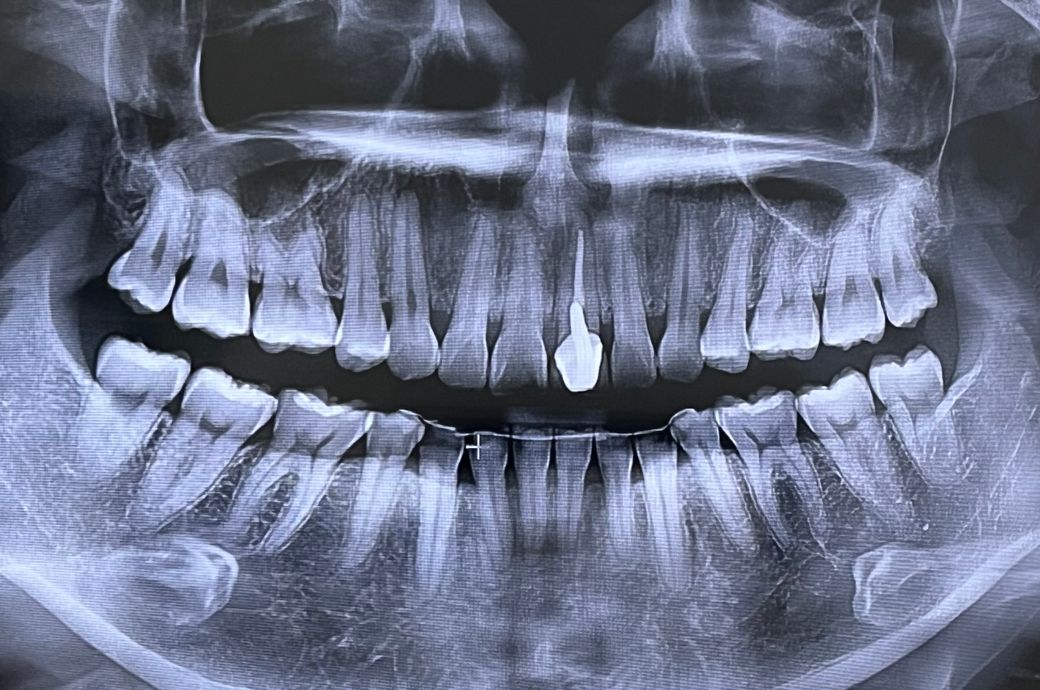

왼쪽 앞니는 어릴 때 크라운했습니다 . 현재 20년 넘게 유지중입니다 . 불편감도 없어요. 외적으로는 치아-잇몸라인이 검게 변한 것뿐입니다.

올해 초에 병원1에서 치아검진했을 때는

약간의 충치만 있고 지켜보잔 소견을 받았는데

최근에 사랑니 발치를 위해 방문한 병원2에서는 크라운한 치아 위쪽에 염증이 큰 범위로 있다하시네요 ㅠㅠ 발치에 대한 두려움으로 경황스러워

발치하고 임플란트에 대한 얘기도 하셨어요 .

아직 젊은데 임플란트라니.. 크라운을 너무 오래 사용해서 그런걸까요..?